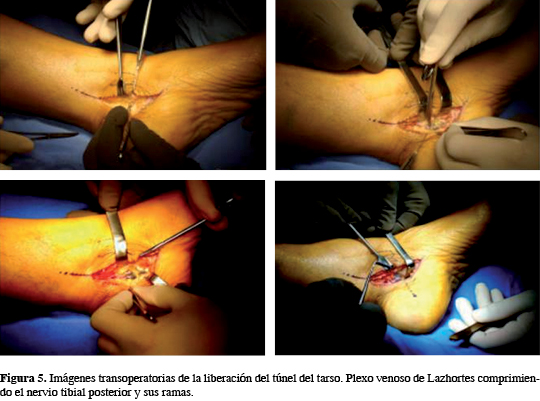

Segunda cirugía (16 de Julio de 2011): Dos meses después de la primera cirugía, se realiza incisión medial, localizando maléolo medial, parte distal y medial del tendón calcáneo y parte inferior del calcáneo. Se incide en "L" de 15 cm aproximadamente de longitud; se diseca por planos, identificando el ligamento lacinado; se incide longitudinalmente y de proximal a distal se diseca, retirando el tejido graso abundante; se localiza plexo venoso tortuoso, donde al incidir el tejido graso se observa una herniación del paquete neurovascular medial del tobillo; se libera el plexo venoso hacia distal, donde se observa atrapamiento del nervio tibial posterior y sus ramas de manera circunferencial, lo que ocasiona la compresión severa; se liga una de las venas del plexo de Lazhortes y se diseca, liberando el paquete intervascular. Se desinserta el músculo abductor del primer dedo, localizando las ramas calcánea medial, plantar lateral y plantar medial; se libera así todo el trayecto del tibial posterior, se retira la isquemia y se realiza hemostasia; se cierra el tejido subcutáneo con Vycril 2-0 y la piel con Nylon 3-0, con puntos simples; se coloca drenaje. Se lava y cubre con gasas estériles y vendaje elástico. Tiempo de cirugía: dos horas; tiempo de isquemia: una hora y media. No hay incidentes (Figura 5).